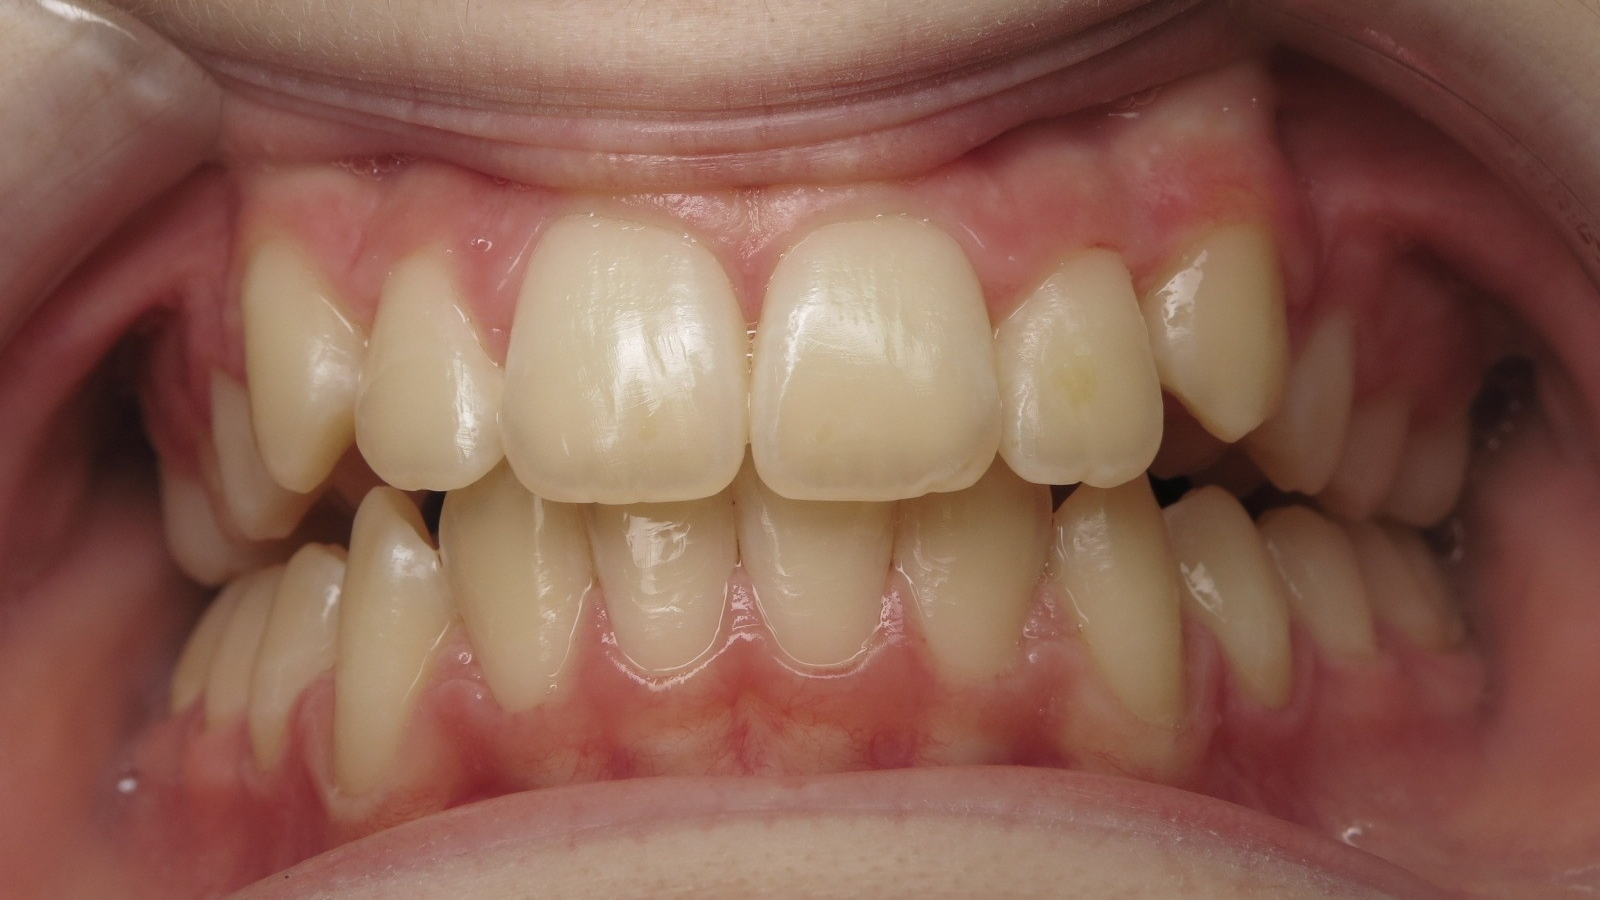

bilan début fin de traitement